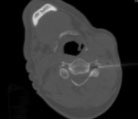

Periradikuläre Injektion Halswirbelsäule (Spritze an die Nervenwurzel unter CT-Kontrolle)

Periradikuläre Injektion Lendenwirbelsäule (Spritze an die Nervenwurzel unter CT-Kontrolle)